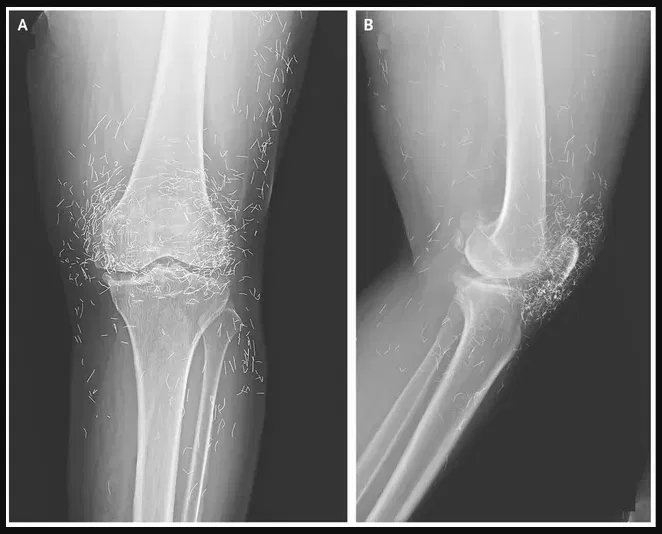

Doctors examining X-rays of a 65-year-old South Korean woman with severe knee pain made a startling discovery: hundreds of tiny gold acupuncture needles embedded in her tissue.

The woman had osteoarthritis, a condition that damages cartilage and bone, causing pain and stiffness. Standard pain relievers and anti-inflammatory drugs offered little relief and caused stomach problems, so she turned to acupuncture. In her case, doctors reported in the New England Journal of Medicine, the needles—presumably gold—were deliberately left in her knees for ongoing stimulation.

Acupuncture, an alternative therapy, uses thin needles inserted at specific points to treat pain and other ailments. In some Asian countries, leaving gold threads or needles around joints is a common arthritis treatment. But experts warn this practice carries risks. Dr. Ali Guermazi, a radiology professor at Boston University, explained that foreign objects can trigger inflammation, abscesses, or infection. They may also interfere with imaging: “The needles may obscure some of the anatomy,” he noted.

Another concern is safety during scans. Patients with embedded needles cannot undergo MRI exams, as the metal could shift and damage blood vessels. “The human body wants to get rid of the foreign object,” Guermazi said, noting the immune system walls it off with fibrous tissue.